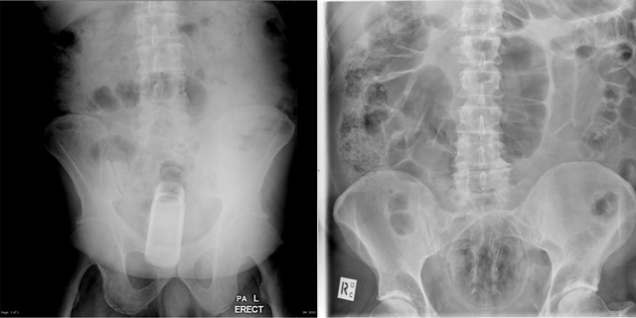

Para pesquisas na internet, geralmente, as pessoas buscam artigos na Wikipedia. Radiologistas procuram em um site um quanto peculiar chamado Radiopaedia. A página reúne imagens de raio-x e, inclusive, mostra partes extremas (e nunca imagináveis) do corpo humano. Essa é a dica da Utilidade da Semana.

A página é um recurso educativo para compartilhar tutoriais e conhecimento sobre tudo que envolve o assunto de radiologia. Para aqueles que não são muito interessados (ou se surpreendem facilmente) por assuntos relacionados a medicina, no topo existe um aviso: “Esse site é dirigido para profissionais médicos e de radiologia, contém conteúdo colaborativo e materiais que podem confundir o público leigo”.